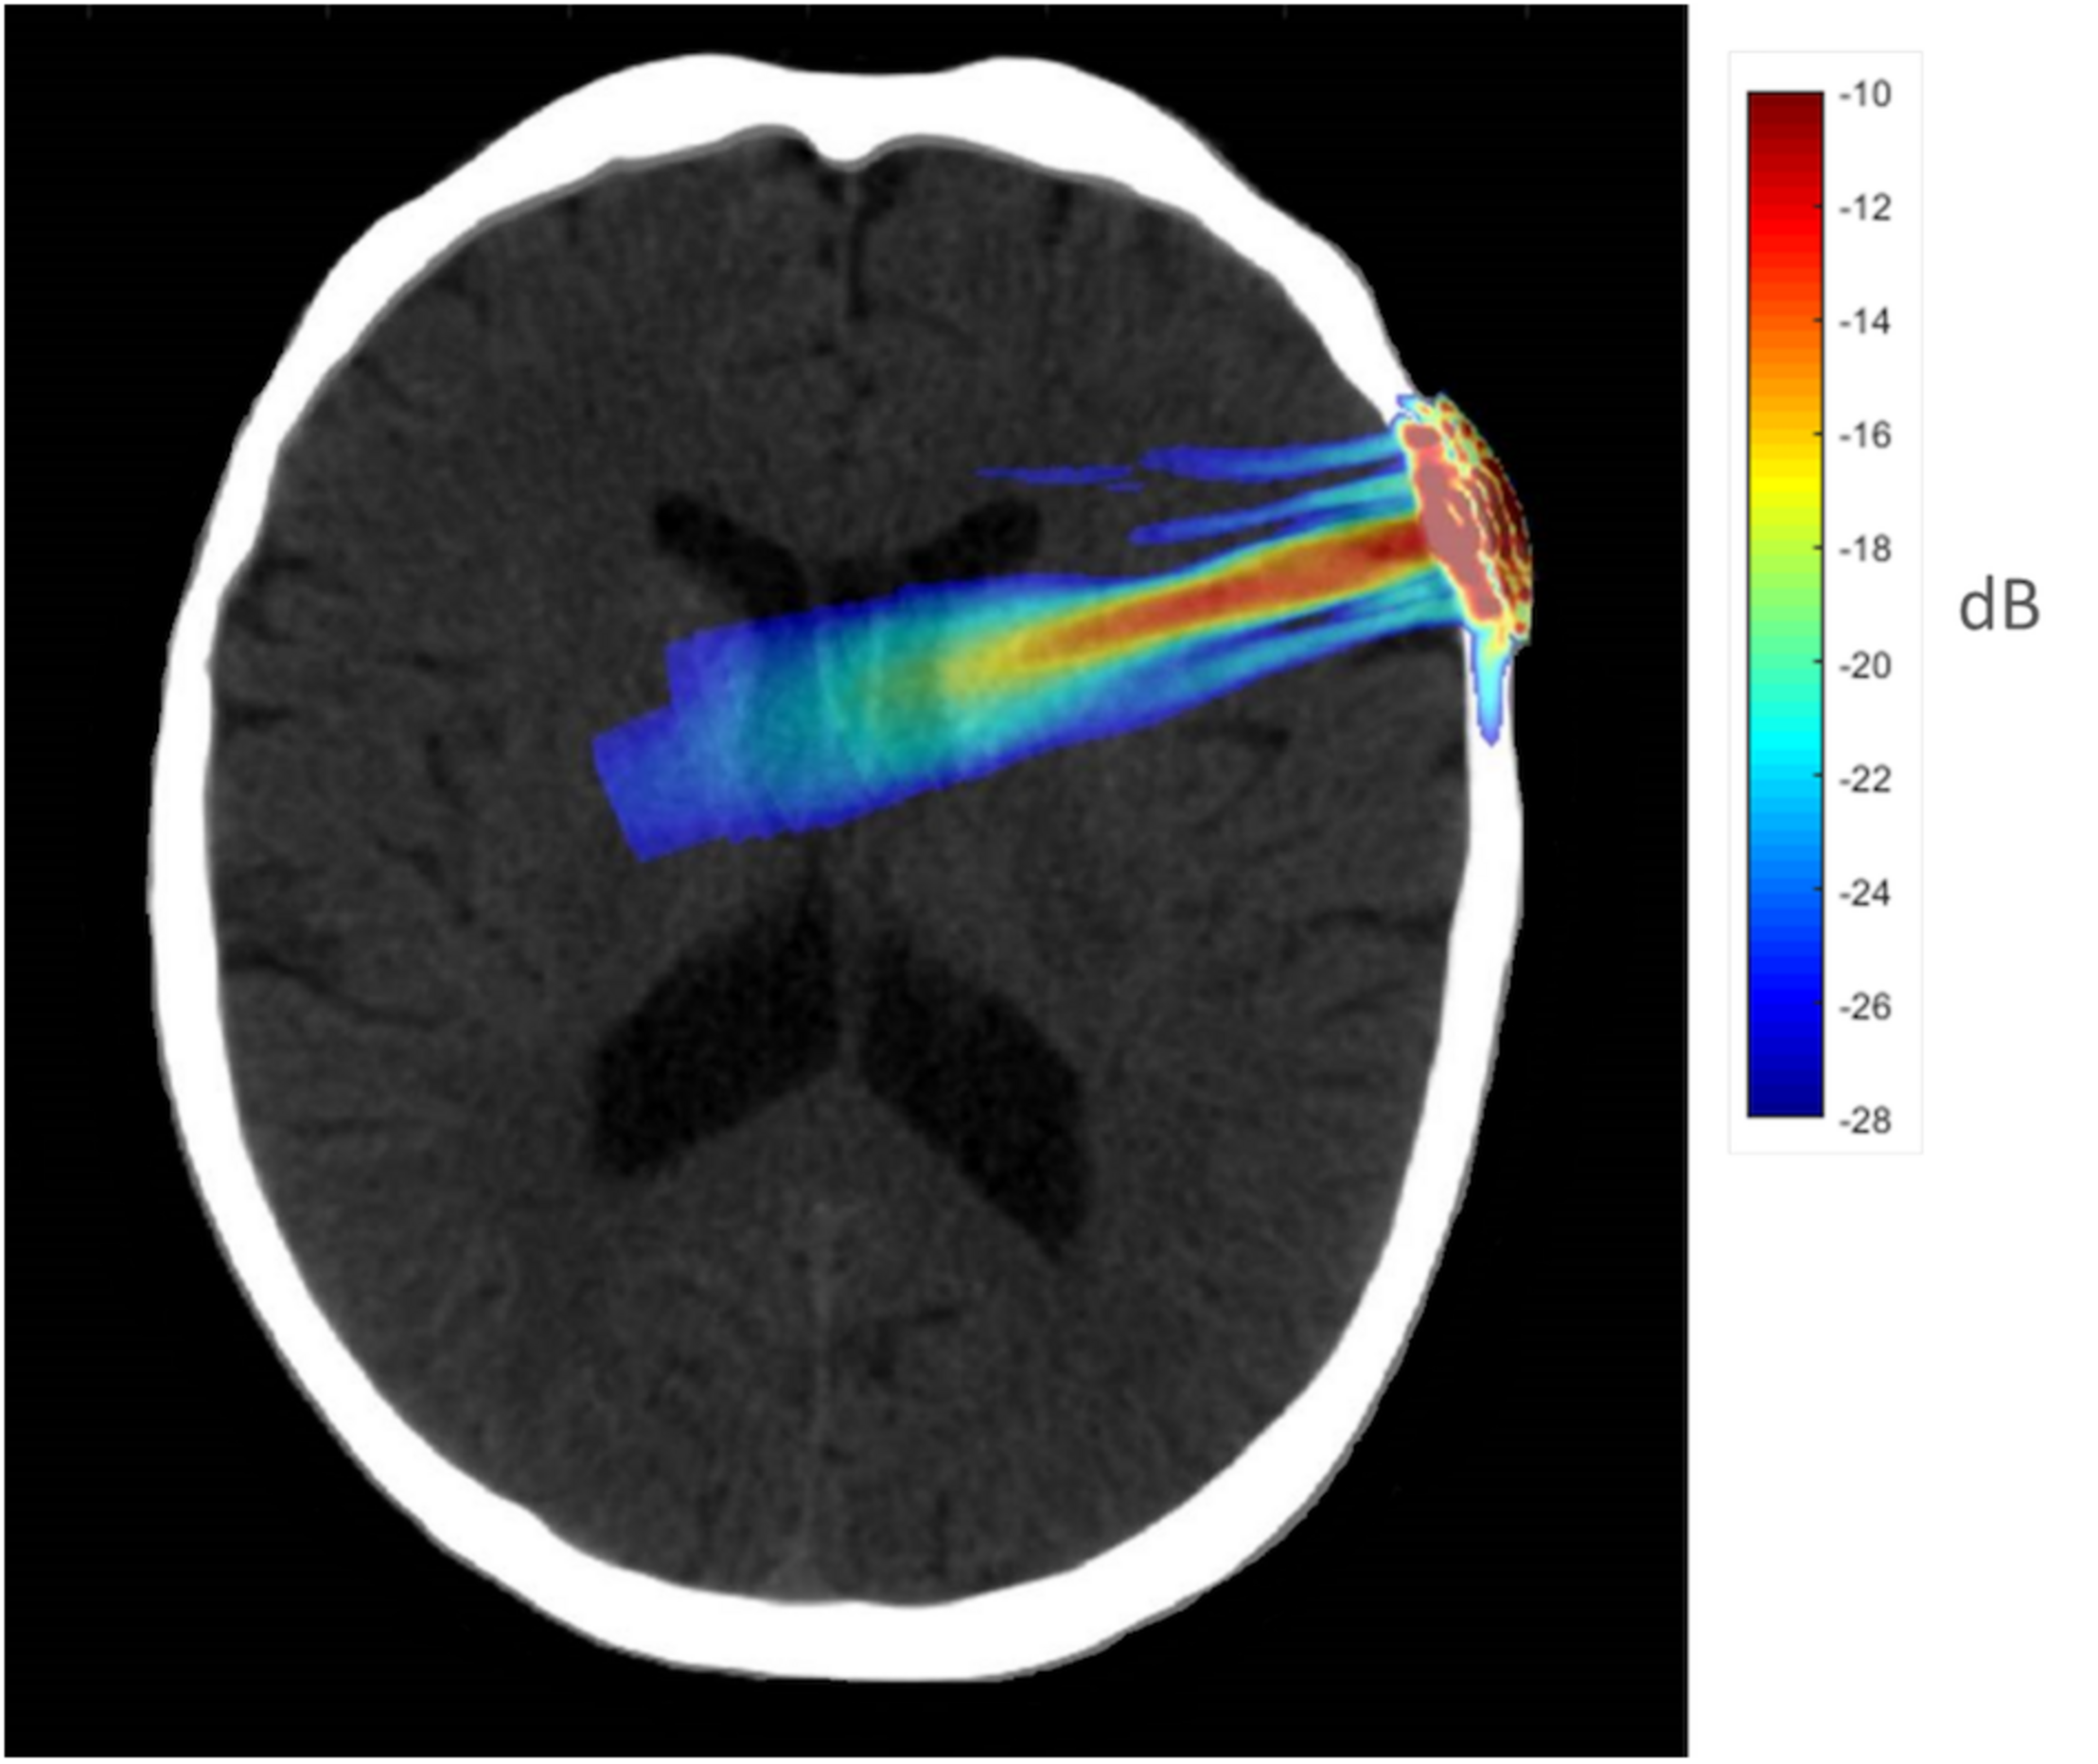

To better understand the tFUS properties of the focal beam, a head model was created using the K-Wave (Treeby and Cox, 2010) toolbox in MATLAB. A CT scan (randomly chosen from the R.I.R.E. project)1 was used to construct the acoustic model of the head. The ultrasound field reported above was entered into the model and projected into the brain assuming the transducer was placed perpendicular to the scalp over F8 (the EEG location centered over the rIFG). The speed of sound entered was 1,550 m/s, and the brain density was 1030 kg/m3. Acoustic simulations were performed with the k-Wave MATLAB toolbox on an archival CT scan to estimate the effects of an individual skull on the ultrasound beam properties targeting the rIFG. Figure 1 displays the simulated ultrasound wave propagation through the skull at the location of F8. In this model, the skull reduced the intracranial max acoustic pressure by 53%.

FIGURE 1

Acoustic simulation model on a representative CT scan of a male patient. The transducer was positioned over the F8 EEG electrode location on the scalp which centers over the rIFG. Hotter colors (red, yellow) indicate more intense sonication, cooler colors (blue, green) indicate less intense sonication.